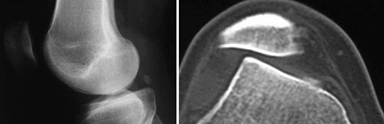

La tomografía es una herramienta importante en la determinación de la congruencia y/o subluxación patelo-femoral, para determinar hipoplasia de la tróclea y para identificar el grado de lateralización de la tuberosidad anterior de la tibia 17,18,23 . Figura 8.

Figura 8. La tomografía muestra que la rodilla derecha, a la izquierda en la figura, a 40º de flexión se subluxa, además se observa la displasia del surco o la tróclea. Fuente: Fotos propias del autor.